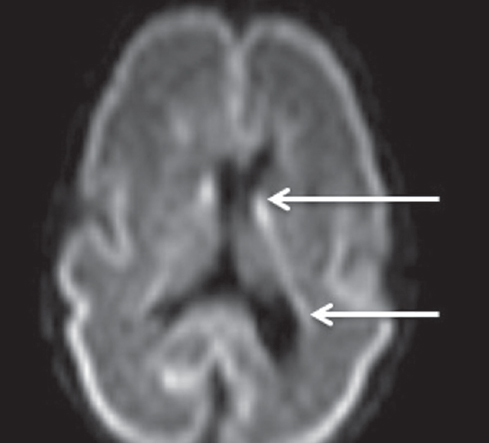

Как видно из таблицы, при выполнении МР-исследования в ПКВ 27–32 недели герминальный матрикс визуализировался у восьми недоношенных детей на ДВИ в виде усиления МР-сигнала вдоль боковых стенок боковых желудочков мозга, а также вдоль передних рогов над хвостатыми ядрами с обеих сторон (рис. 4). На Т2 ВИ герминальный матрикс достоверно выявлен у семи новорожденных (рис. 5). На Т1 ВИ герминальный матрикс достоверно выявлен у двух новорожденных (рис. 6). На последовательностях FLAIR герминальный матрикс не визуализировался.

Рис. 5. МРТ головного мозга недоношенного ребенка (ПКВ 28 недель). Т2 ВИ, аксиальная проекция, стрелками выделены участки герминального матрикса, расположенного вдоль наружных стенок боковых желудочков, гипоинтенсивный МР-сигнал

Fig. 5. MRI of preterm newborn (PCA 28 weeks), Т2-WI, axial plane. Arrows mark the areas of the germinal matrix located along the external walls of the lateral ventricles (hypointense MR signal)

У новорожденных, которым МРТ проводили с 33-й по 34-ю неделю ПКВ, герминальный матрикс визуализировался у двух пациентов на ДВИ в виде слабого повышения МР-сигнала вдоль боковых стенок боковых желудочков мозга (рис. 7). На остальных импульсных последовательностях герминальный матрикс не определялся.

Рис. 7. МРТ головного мозга недоношенного ребенка (ПКВ 34 недели). ДВИ, аксиальная проекция, герминальный матрикс визуализируется вдоль наружных стенок боковых желудочков (отмечен стрелками)

Fig. 7. MRI of preterm newborn (PCA 30 wks.), DWI, axial plane. The germinal matrix is visualized along the external walls of the lateral ventricles (marked by arrows)